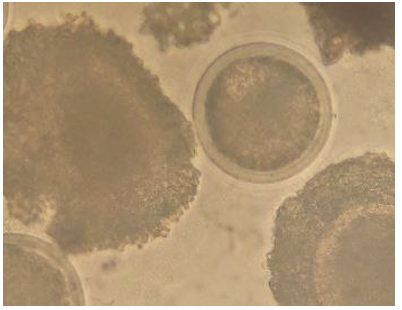

Second step, remove all non-viable oocytes, and then using the khudhory red to evaluate viability of oocytes. Then, these oocytes (viable) are left to die, by leaving them in unsuitable conditions such as low\ high temperatures or medium without nutrients outside the incubator [18], [19] [20]. Third step, again stain with khudhory red, unstained oocytes, the stain cannot inter cytoplasm are viable (live)(figure 11A), and full stain oocytes, the khudhury red pass through membrane by porous and penetrate cytoplasm (red in colour) are non-viable (dead)(figure 11B) [21], [22], [23].

Thus, it is said that every oocyte that acquires a red color is dead (non-viable), and any oocyte that does not acquire a red color is a live (vible).

Figure 12. Non-Viable Oocyte (dead) After Khudhory Red